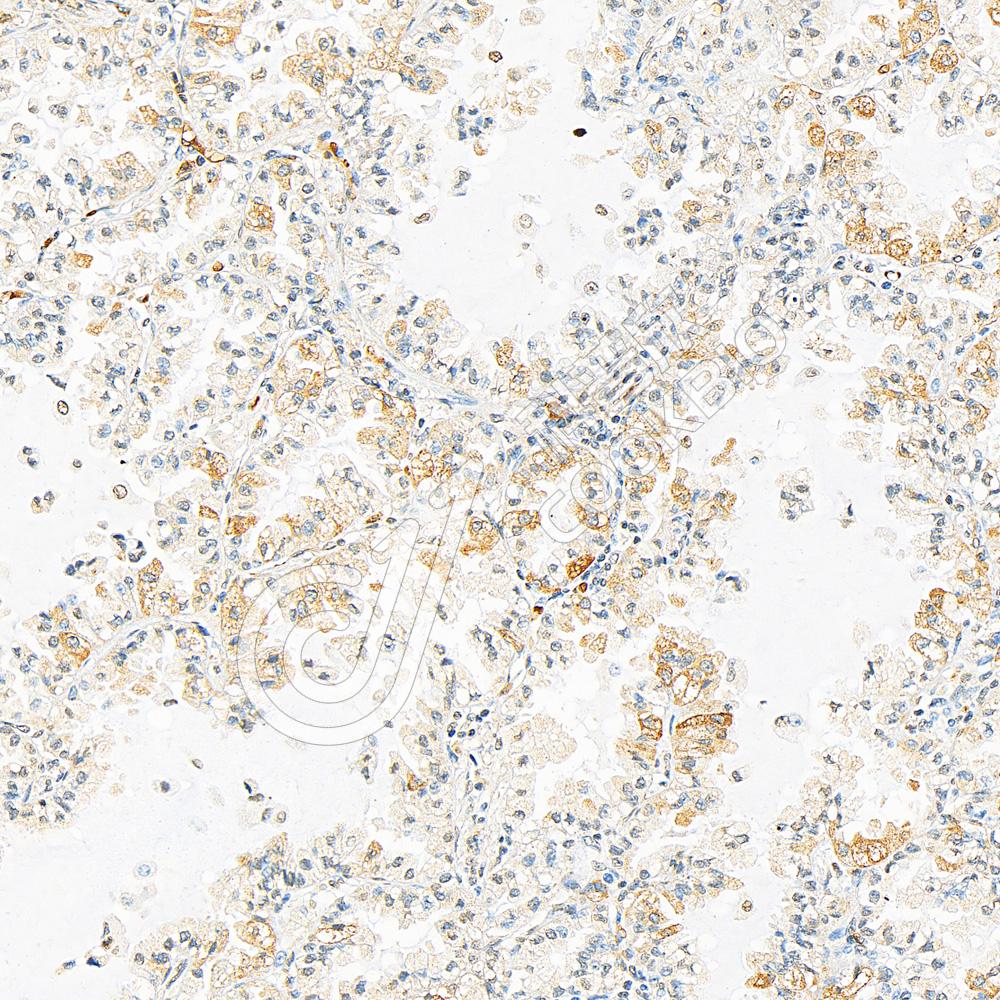

IHC检测SQSTM1/p62蛋白(货号 K134593).

样品: 人肺癌, 4%多聚甲醛 (货号KSG1101) 固定12-24小时.

抗原修复: 柠檬酸抗原修复液(干粉, pH 6.0) (KSG1201), 98℃, 20分钟.

—抗: 1: 800稀释, 4℃ 孵育过夜.

二抗: S-vision免疫组化多聚二抗(山羊抗兔),即用型 (货号KB3906), 室温孵育20分钟.